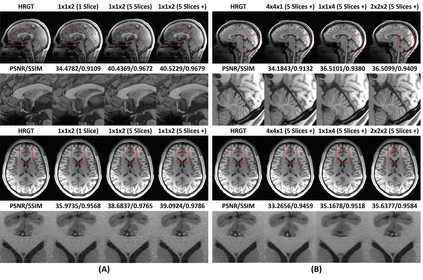

Shortening acquisition time and reducing the motion artifacts are two of the most essential concerns in magnetic resonance imaging. As a promising solution, deep learning-based high-quality MR image restoration has been investigated to generate highly-resolved and motion artifact-free MR images from lower resolution images acquired with shortened acquisition time or motion artifact-corrupted images. However, numerous problems still exist to prevent deep learning approaches from becoming practical in the clinic environment. Specifically, most of the prior works focus solely on the network but ignore the impact of various down-sampling strategies on the acquisition time. Besides, the long inference time and high GPU consumption are also the bottlenecks to deploy most of the prior works in clinics. Furthermore, prior studies employ random movement in retrospective motion artifact generation, resulting in uncontrollable severity of motion artifact. More importantly, doctors are unsure whether the generated MR images are trustworthy, making diagnosis difficult. To overcome all these problems, we adopted a unified framework of 2D deep learning neural network for both 3D MRI super-resolution and motion artifact reduction, demonstrating such a framework can achieve better performance in 3D MRI restoration tasks compared to other state-of-the-art methods and remain the GPU consumption and inference time significantly low, thus easier to deploy. We also analyzed several down-sampling strategies based on the acceleration factor, including multiple combinations of in-plane and through-plane down-sampling, and developed a controllable and quantifiable motion artifact generation method. At last, the pixel-wise uncertainty was calculated and used to estimate the accuracy of the generated image, providing additional information for a reliable diagnosis.